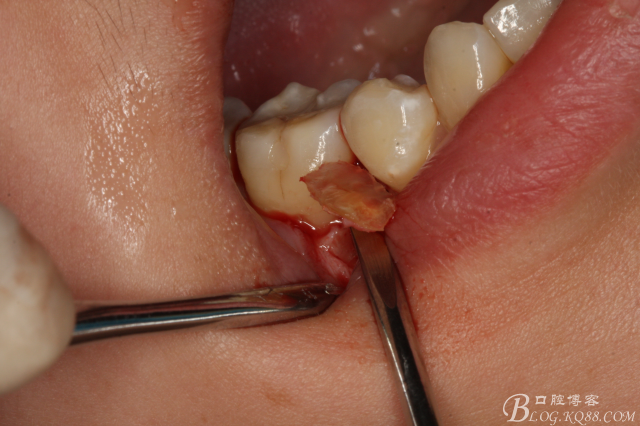

圖8.高速球鉆去骨約3mm.

圖9.暴露45頰側(cè)根面約1/2.牙根與44、46牙根緊緊相鄰。無法直接用挺。

圖10.高速裂鉆垂直分根

圖11.形成牙根中央一個約5mm長、2mm寬溝槽。